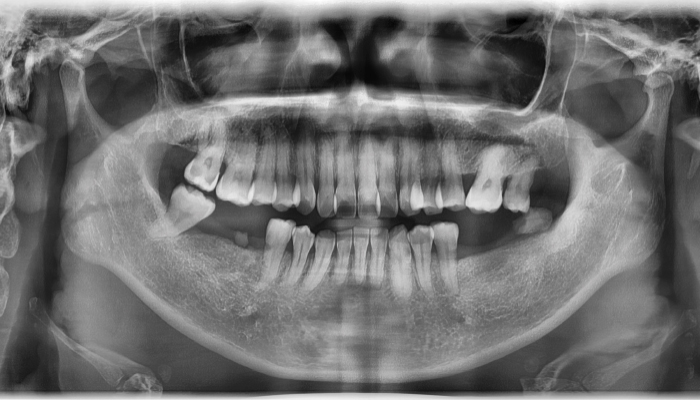

상악동거상술 전후 사례

• 식립 전

식립 후